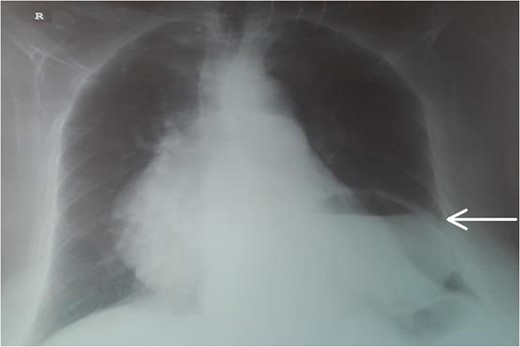

An 87-year-female patient was admitted to emergency department complaining about vomiting for the past 7 days with mild abdominal pain. The patient was hemodynamically stable, had sluggish bowel sounds and soft abdominal wall with mild tenderness. The patient also suffered from atrial fibrillation, heart failure, myelodysplastic syndrome, hiatus hernia and cholelithiasis. The findings of the laboratory tests were unremarkable. Plain chest and abdominal radiograms revealed hiatus hernia with gastric dilation (Fig. 1), a few air-fluid levels and pneumobilia, with delineation of extrahepatic and intrahepatic bile ducts by air (Fig. 2). A nasogastric tube was inserted, which drained biliary content. An abdominal computed tomography (CT) scan revealed the presence of air in the intrahepatic bile ducts, free air and leakage of oral contrast agent in the hepatic hilum and subhepatic space and an impacted gallstone in the third portion of the duodenum (Figs 3 and 4). The diagnosis of cholecystoenteric fistula and proximal gallstone ileus was set.

Chest radiogram. The arrow shows the dilated intrathoracic stomach.